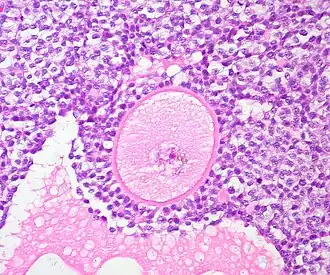

- Culture the cortical ovarian tissue to enhance primordial follicle (immature follicle) growth and isolate the primordial and primary follicles

Culturing of cortical ovarian tissue and isolation of follicles

A common source of ovarian tissue used comes from tissue excised from the patient prior to cancer treatment, which is then cryopreserved.[7] The tissue is then cultured to activate the primordial follicles and allow them to develop.[2] To isolate the follicles, a combination of enzymatic and mechanical tissue digestion has shown to be the most effective method to yield a high quantity of follicles whilst maintaining their quality.[8] The enzymes used, liberase DH and DNase, are produced by good manufacturing practice (GMP) to fully comply with GMP guidelines to ensure future application to patients. The enzymatic digestion process is inactivated every 30 minutes and the suspension is filtered to allow fully isolated follicles to be removed and reduce unnecessary enzyme exposure which may lead to damage of their basement membrane and their death.[8]

When recovering the isolated follicles, malignant cells may be inadvertently retrieved, which poses the risk of re-introducing malignant cells into the patient.[8] To minimise the risk of contamination, the isolated follicles undergo a washing step which involves rinsing the follicles with fresh dissecting media, three times, to separate them from surrounding isolated cells.[2][8]